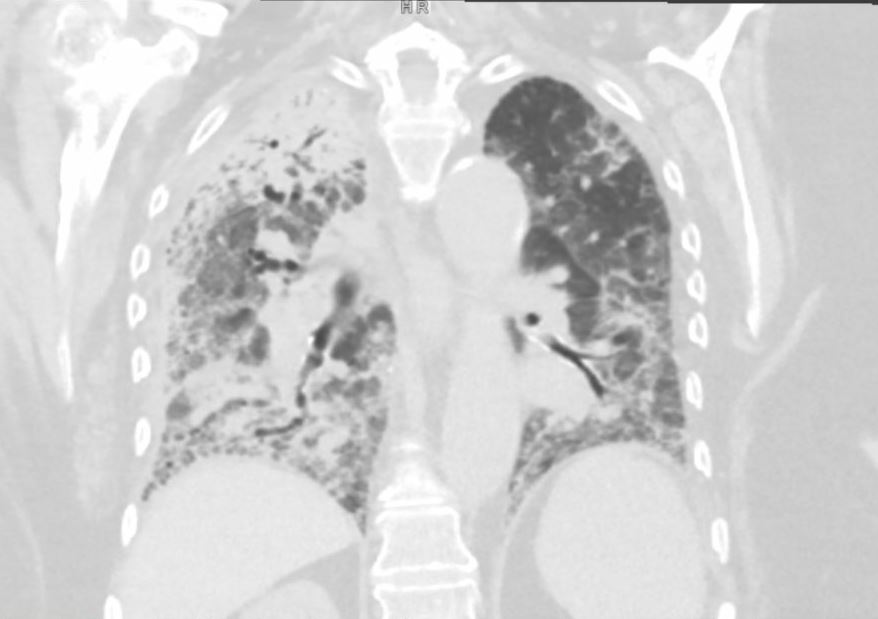

Case Presentation: An 89-year-old female with a history of heart failure with reduced ejection fraction (HFrEF), atrial fibrillation, and prior left atrial appendage occlusion (Watchman) presented with altered mental status and generalized weakness. On admission, she required intensive care unit (ICU) support, including vasopressors and BiPAP for acute respiratory failure and septic shock. She briefly required vasopressor therapy, and was successfully weaned off, though her oxygen requirements remained elevated, necessitating ongoing BiPAP for hypoxia and hypercarbia.The patient remained afebrile but tachycardic, with a predominant rhythm of atrial fibrillation with rapid ventricular response. Initial workup revealed a negative expanded respiratory viral panel. Chest X-ray showed bilateral infiltrates, and a subsequent chest CT identified ground-glass opacities in the right upper, middle, and lower lobes and left lower lobes, concerning for multifocal pneumonia.Blood cultures initially grew Gram-negative rods, later identified as nontypeable Haemophilus influenzae (NTHi), resistant only to trimethoprim-sulfamethoxazole. She was started on empirical vancomycin and piperacillin-tazobactam. Throughout her prolonged six-week hospitalization, the patient experienced intermittent hypoxia, requiring brief ICU transfers for BiPAP. Ultimately, she was weaned to three liters of oxygen and discharged to a rehabilitation facility in a stable condition.